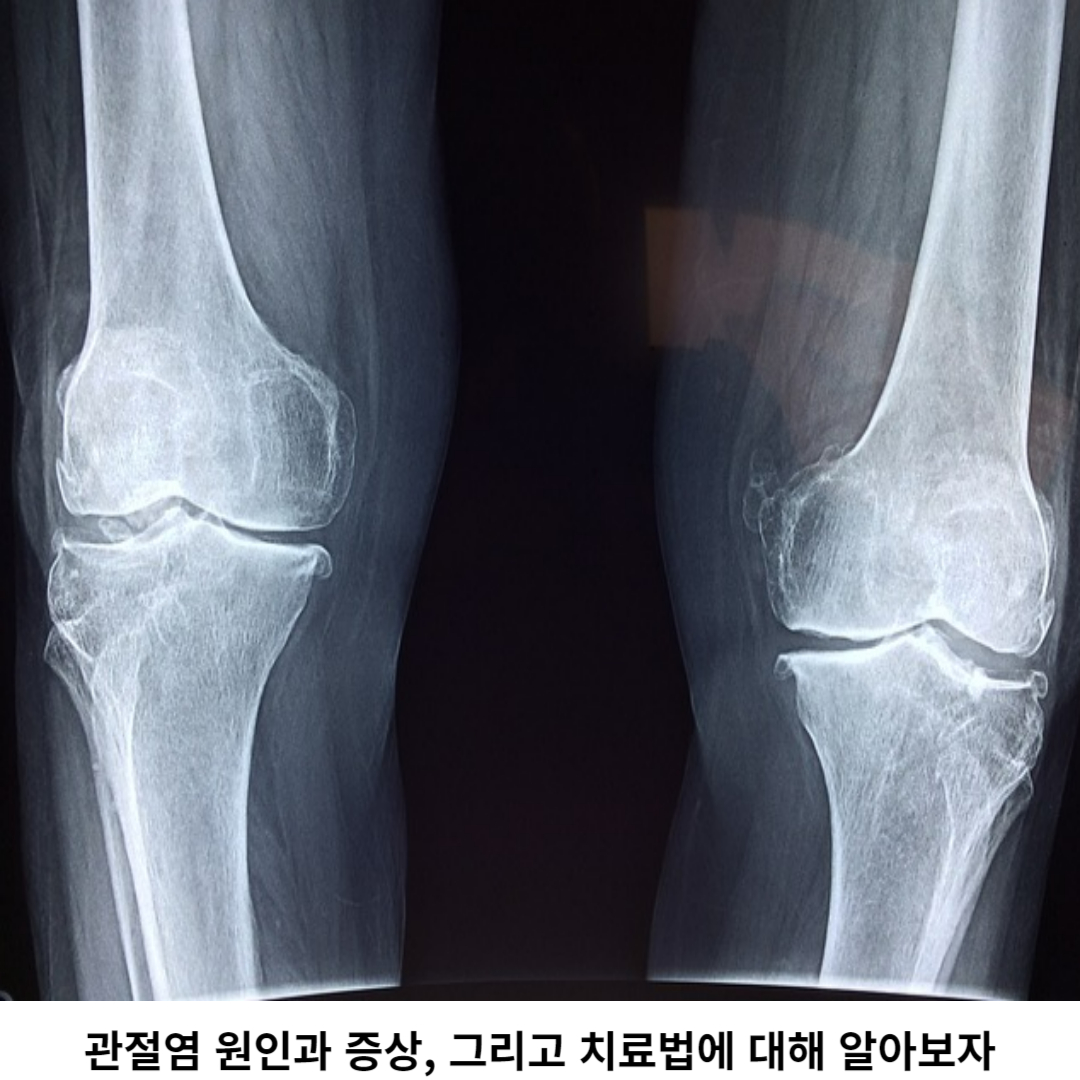

관절염은 인체의 관절 부위에서 발생하는 만성적인 염증 질환으로, 주로 관절 주변의 연골과 뼈조직에 영향을 미칩니다. 이 염증은 일상생활이나 관절을 움직일 때 통증, 기능 저하 등 여러 가지 증상으로 발생될 수 있습니다.

관절염은 여러 가지 원인에 의해 발생할 수 있으며, 연령, 유전적인 요인, 관절 손상, 면역 질환 등이 원인은 여려가지입니다. 관절염은 치료하지 않으면 진행이 지속되어 관절 손상이 발생됩니다. 관절염은 조기 진단과 치료가 매우 중요합니다.